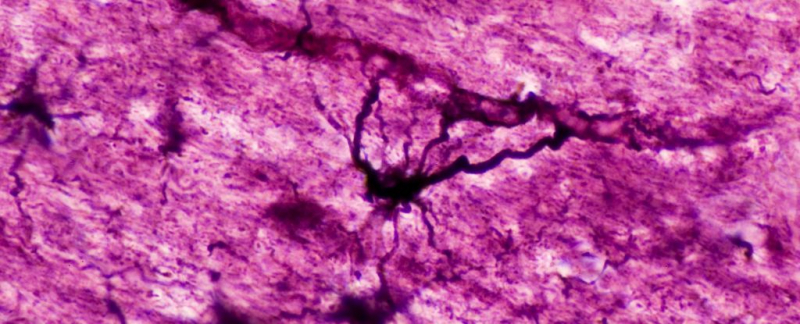

Международная группа ученых сделала новаторское открытие в области нейронаук. Они выделили новый тип клеток мозга, известных как глутаматергические астроциты, которые обладают свойствами как нейронов, так и астроцитов. Эти уникальные гибридные клетки играют активную роль в неврологических функциях, одновременно обеспечивая поддержку окружающим нервным тканям.

Используя секвенирование РНК одной клетки, исследователи выявили девять различных кластеров астроцитов в гиппокампе мозга мыши. Один из них, известный как кластер № 7, выделялся своей локализацией в определенных областях гиппокампа и способностью упаковывать глутамат для высвобождения.

С помощью визуализации глутамата на живых мышах ученые обнаружили, что эти специализированные клетки выделяют глутамат в точных точках, напоминающих синапсы, где нейроны общаются друг с другом. Это позволяет предположить, что глутаматергические астроциты модулируют активность нейронов и контролируют уровень связи и возбуждения между нейронами.